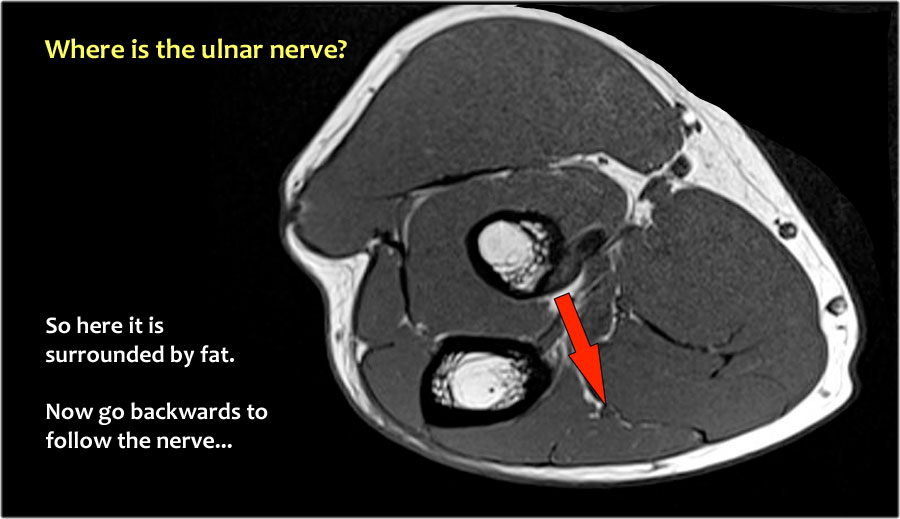

Một cách để thực hiện là đi theo các cấu trúc về phía xa cho đến khi tìm thấy dây thần kinh trụ ở phía xa tại vị trí bình thường của nó ở vùng cẳng tay gần được bao quanh bởi mô mỡ.

Sau đó khi bạn theo dõi nó về phía gần, bạn sẽ nhận thấy rằng đây là một trường hợp chuyển vị dưới da.